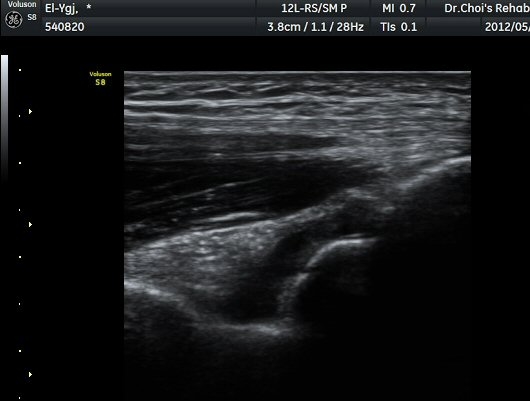

ÆÈ²ÞÄ¡ ¿ÜÃø Á¾´Ü¸é°Ë»ç¿¡¼­ ¼ÒµÎ ¾ÕÂÊ¿¡ ¼ö¾×Àú·ù°¡ °üÂûµÈ´Ù(±×¸² 1).